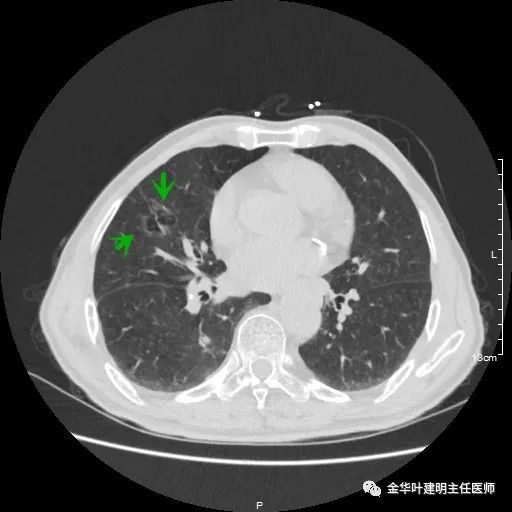

金华的某A,今年已经80岁了,前些天检查发现右下肺部占位,让我会诊。我打开电脑一看图,发现右下肺是典型的实性分叶状的占位,基本可肯定肺癌,余肺仍有多处磨玻璃影及类似慢性炎的病灶,是不是合并炎症?还是多原发肺癌?鉴于其中叶肺门部混合磨玻璃结节边缘略显模糊,为了防止炎性病灶,让其进行了10天的静脉抗炎治疗,但复查靶扫描后发现病灶无任何吸收好转,靶扫描上把细节显示的更清楚了,反而更坚定了我判断其为肺癌的结论。对于这样年纪的多原发癌,我们该如何来进行临床思考呢?治疗该如何建议与决策?当然最后的结果要如实告知患方后,由他们自己决定。

以上示右肺中叶病灶3。是混合磨玻璃结节,位置差,邻近肺门部,无法局部楔形切除,抗炎治疗后靶扫描显示了更清楚的细节,是典型的肺癌影像特征(此处未另提供)。从单病灶来看,需要行右肺中叶切除并清扫淋巴结才能得以治疗。

以上示右中叶病灶4。也是囊腔型病灶,病灶大,囊壁是磨玻璃密度,亦是较为典型的囊腔型肺癌影像。单病灶看,需中叶切除来治疗,因病灶3的存在,中叶切除可同时解决病灶3与病灶4。